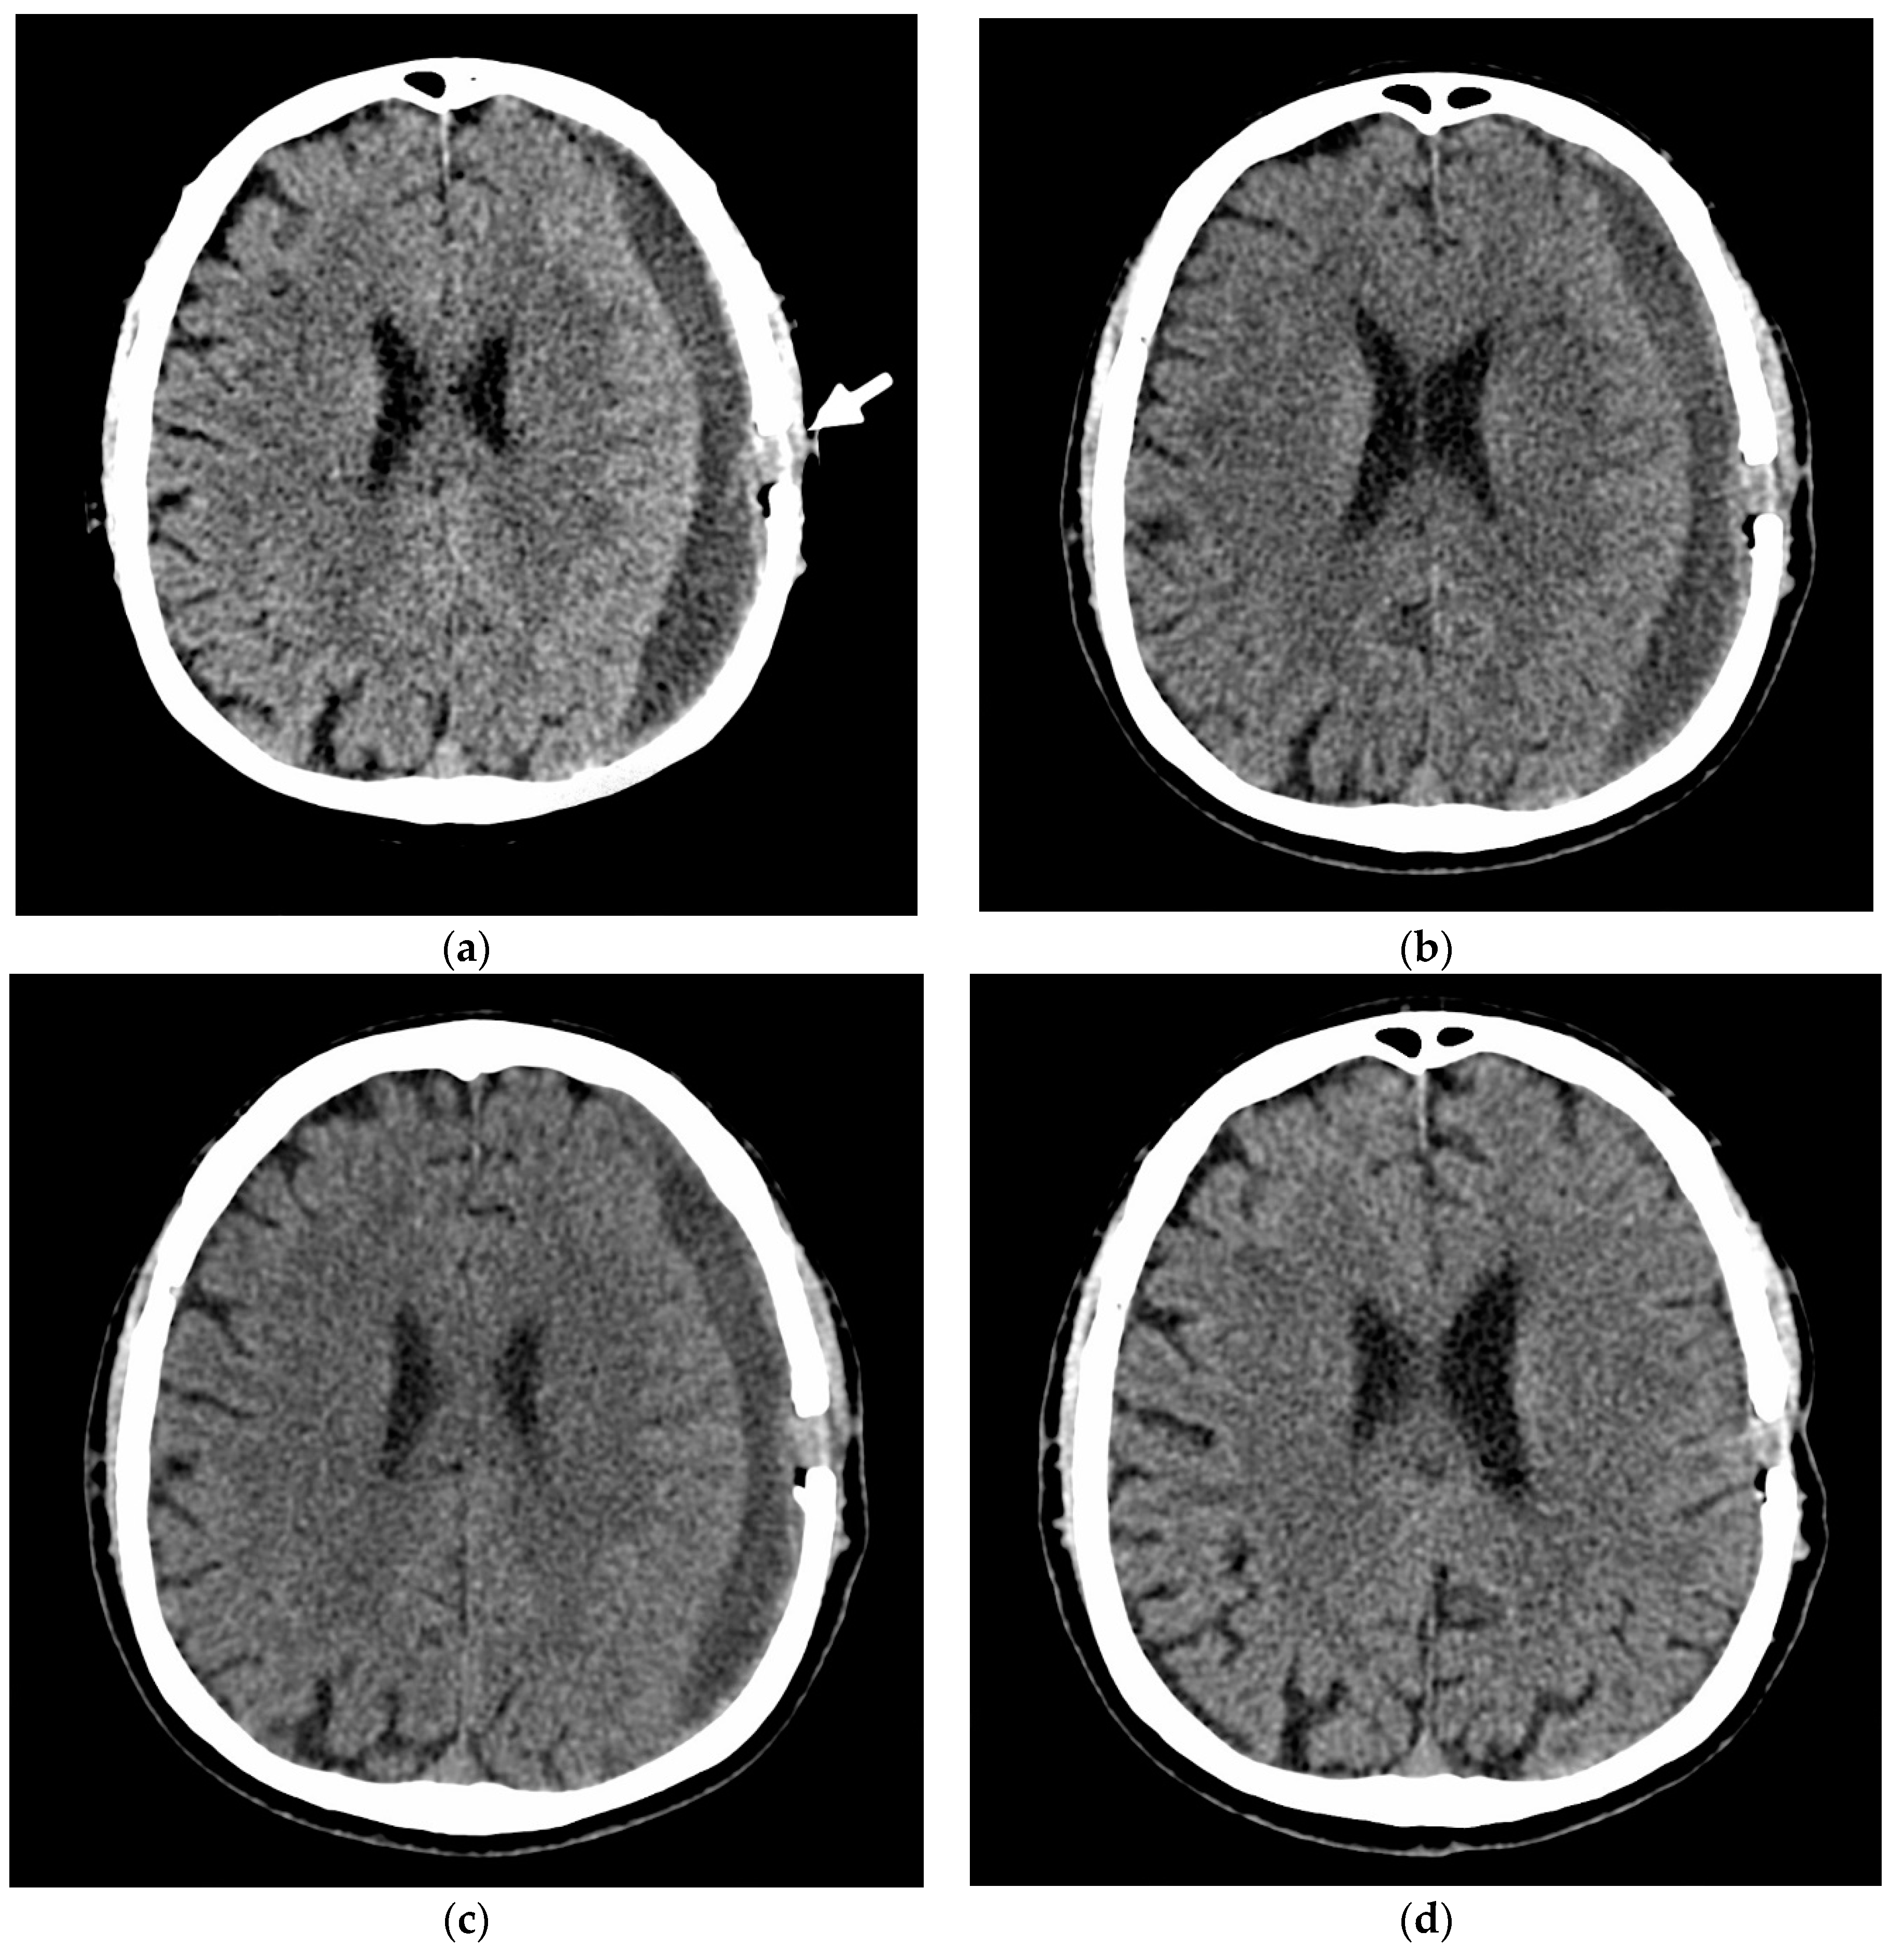

- A 70-year-old patient with left-handed CSDH and a midline shift of 12 mm, motor aphasia, and right-hand hemiparesis.

- A 42-year-old patient with bilateral CSDH that progressively increased during 1.5 months from 54 mL to 69 mL on the right-hand side and from 68 mL to 83 mL on the left-hand side, causing significant compression of both hemispheres and neurological deterioration.

- An 89-year-old patient with bilateral CSDH (no midline shift). There was no apparent connection with an antecedent head injury. However, the patient’s relatives reported that the patient did periodically fall. At the time of admission, the patient presented tetraparesis and a decreased level of consciousness.

3.3.2. Efficacy Endpoint

3.4. Illustrative Cases